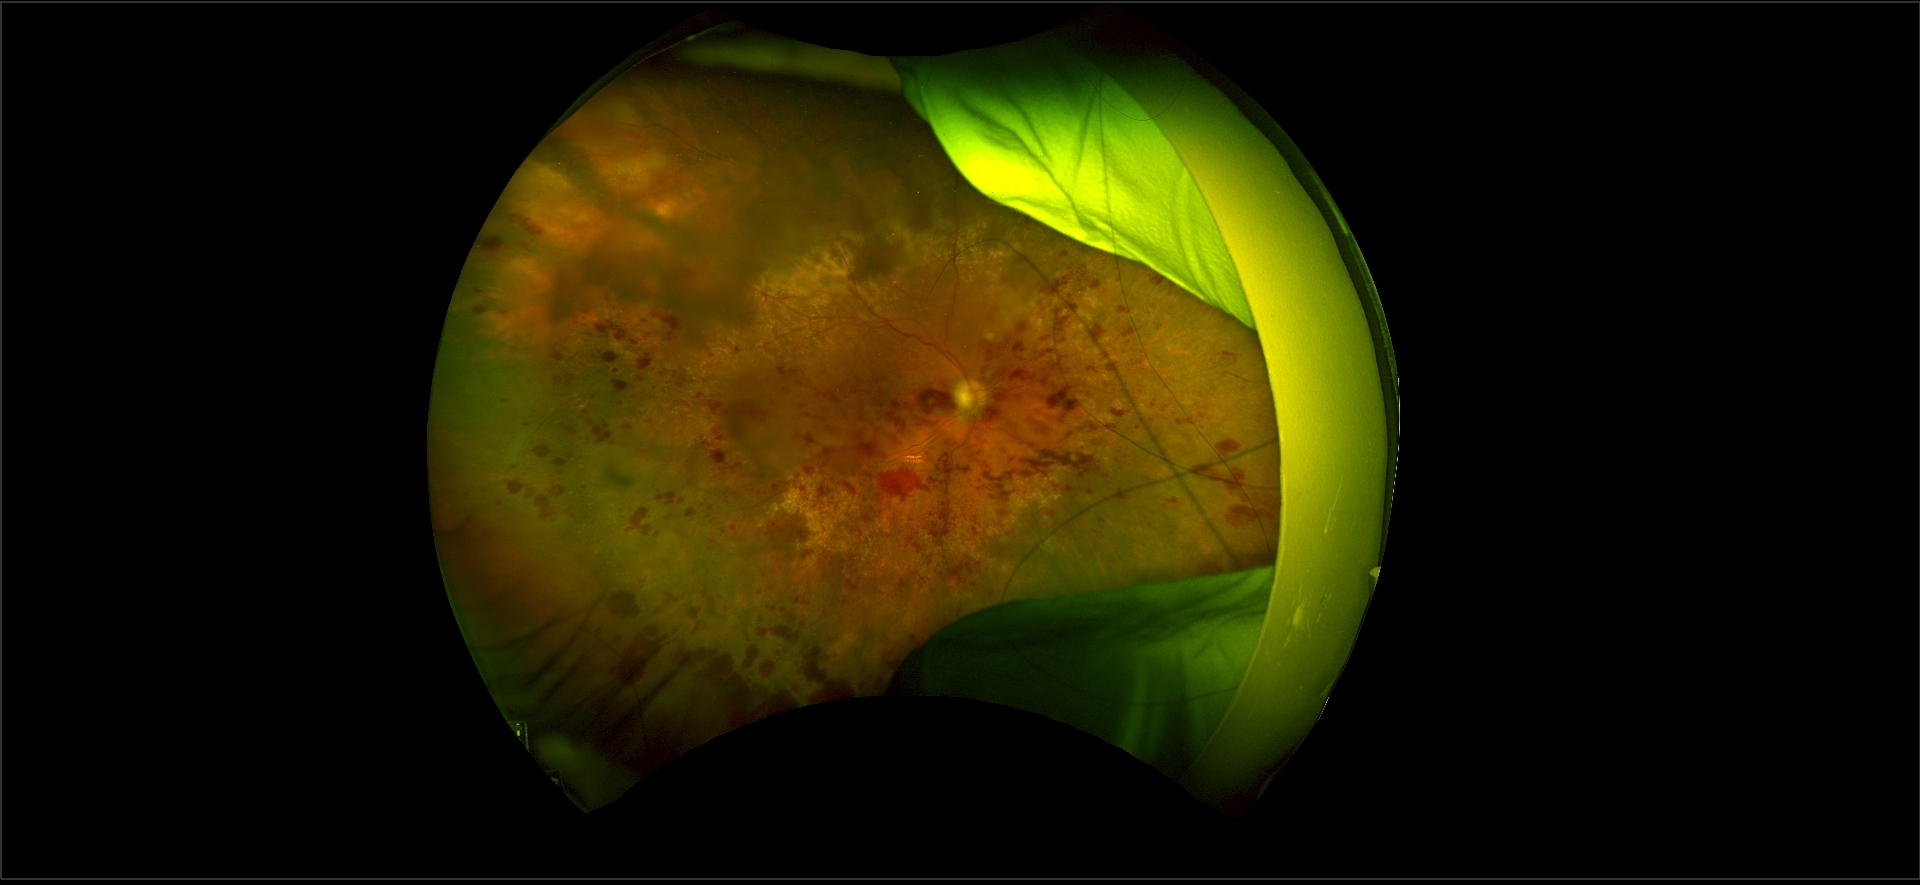

After Maria received her pacemaker and was feeling better, she returned to Dr. Li and started monthly intravitreal injections (eye injections) to treat macular edema caused by a retinal vein occlusion, in which narrowed veins cause a blockage that restricts blood drainage and leads to fluid building up in the center of vision, limiting vision. “High blood pressure is a major risk factor for retinal vein occlusions, which is often unrecognized by the patient,” Dr. Li said. “I routinely check blood pressure in patients who present with vein occlusions, but I wasn’t expecting a routine check of Maria’s vitals to uncover an urgent heart issue.”

The regular eye injections have made a significant difference in Maria’s vision and Dr. Li’s care has meant the world to Maria and her family. “My Mom and I can both see the difference the injections are making when we see the imaging in Dr. Li’s office and even though her vision will never be perfect, it has improved,” Evelyn said. “I have also experienced a retinal issue and I tell everyone that will listen not to ignore their vision and to see a retina specialist right away if something doesn’t seem right.”